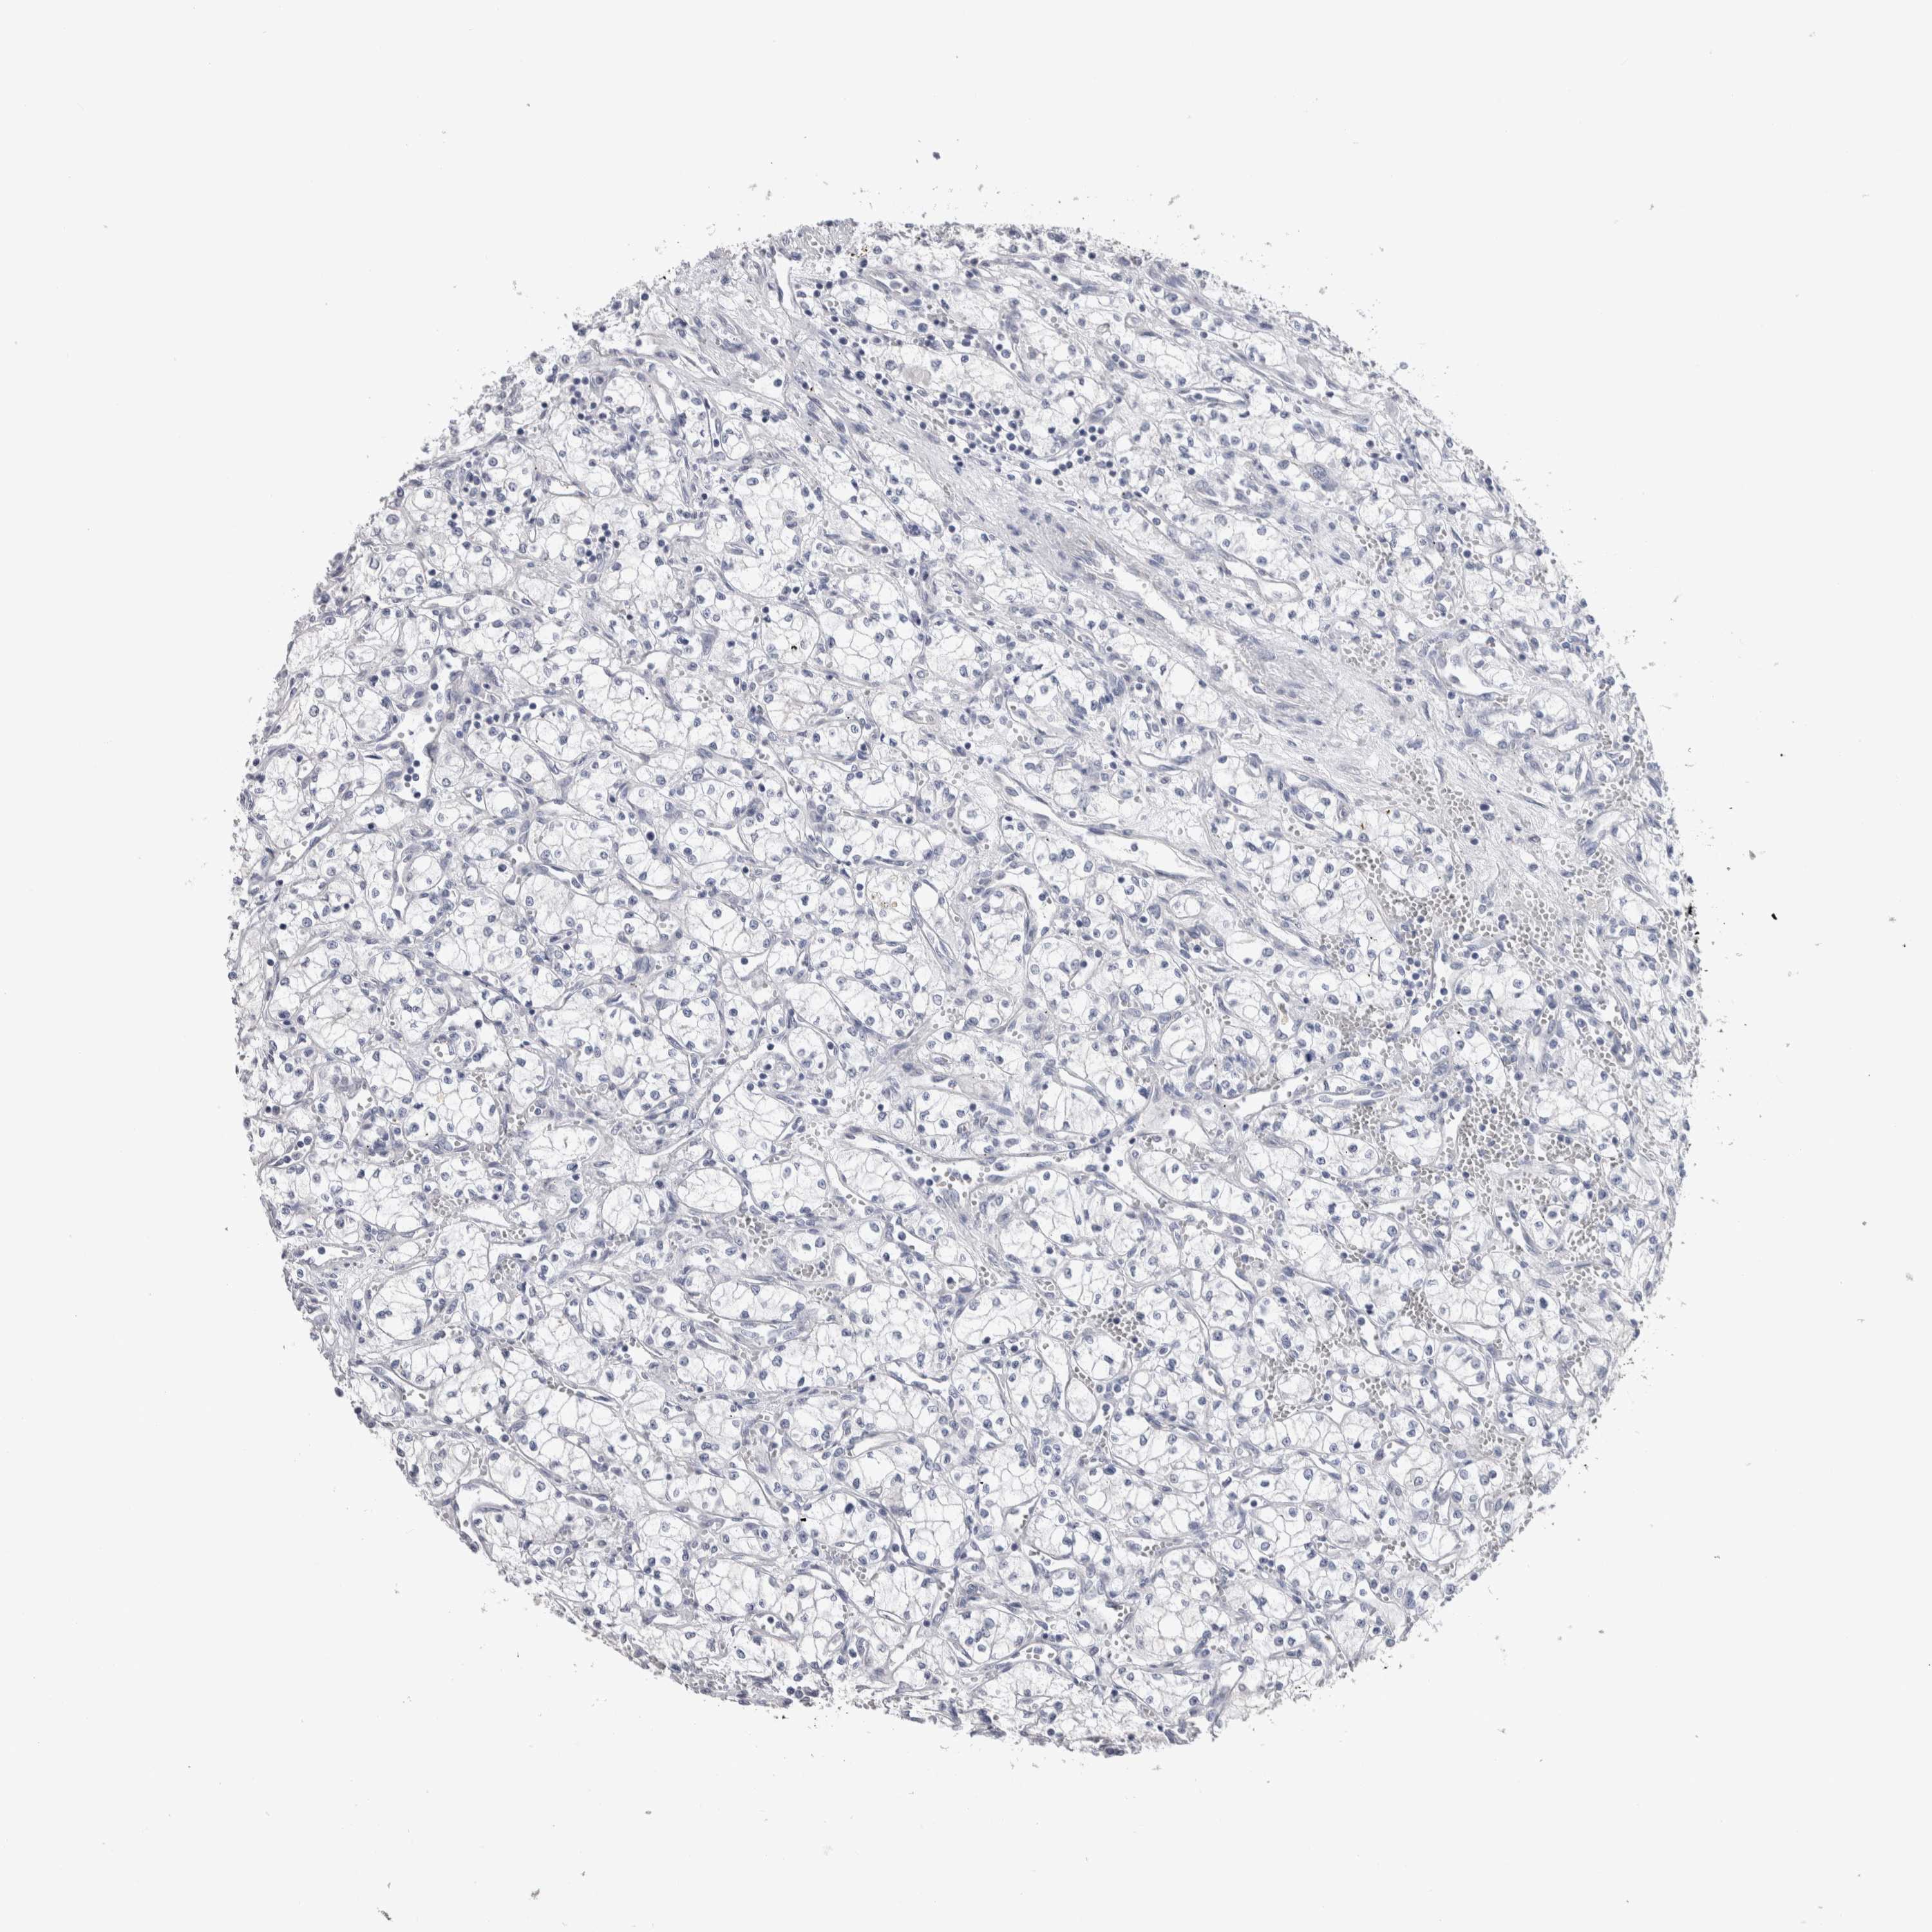

KIDNEY RENAL CLEAR CELL CARCINOMA (VALIDATION) - Interactive survival scatter ploti

The Survival Scatter plot shows the clinical status (i.e. dead or alive) for all individuals in the patient cohort, based on the same data that underlies the corresponding Kaplan-Meier plots. Patients that are alive at last time for follow-up are shown in blue and patients who have died during the study are shown in red.

The x-axis shows the expression levels (FPKM) of the investigated gene in the tumor tissue at the time of diagnosis. The y-axis shows the follow-up time after diagnosis (years). Both axes are complimented with kernel density curves demonstrating the data density over the axes. The top density plot shows the expression levels (FPKM) distribution among dead (red) and alive patients (blue). The right density plot shows the data density of the survived years of dead patients with high and low expression levels respectively, stratified using the cutoff indicated by the vertical dashed line through the Survival Scatter plot. This cutoff is automatically defined based on the FPKM cutoff that minimizes the p-score. The cutoff can be changed by dragging the vertical line or by entering a cutoff value in the square labeled "Current cut-off".

Under the Survival Scatter plot the p-score landscape (black curve; left axis) is shown together with dead median separation (red curve; right axis). Dead median separation is the difference in median mRNA expression between patients who have died with high and low expression, respectively. It is calculated as follows: median FPKM expression of dead patients with high expression - median FPKM expression of dead patients with low expression. This is intended to aid the user in visually exploring custom cutoffs and the associated p-scores and dead median separation.

Individual patient data is displayed and can be filtered by clicking on one or more of the category buttons on the top of the page. Categories describing expression level and patient information include: high, low, alive, dead, female, male and tumor stages. The scale of the x-axis can be toggled between linear and log-scale by clicking on the "x log" button. Mouse-over function shows TCGA ID, patient information and mRNA expression (FPKM) for each patient.

& Survival analysisi

Kaplan-Meier plots summarize results from analysis of correlation between mRNA expression level and patient survival. Patients were divided based on level of expression into one of the two groups "low" (under cut off) or "high" (over cut off). X-axis shows time for survival (years) and y-axis shows the probability of survival, where 1.0 corresponds to 100 percent.

TMEM102 is not prognostic in Kidney Renal Clear Cell Carcinoma (validation)

: 3.56

Average pTPM 3.9

Number of samples 100